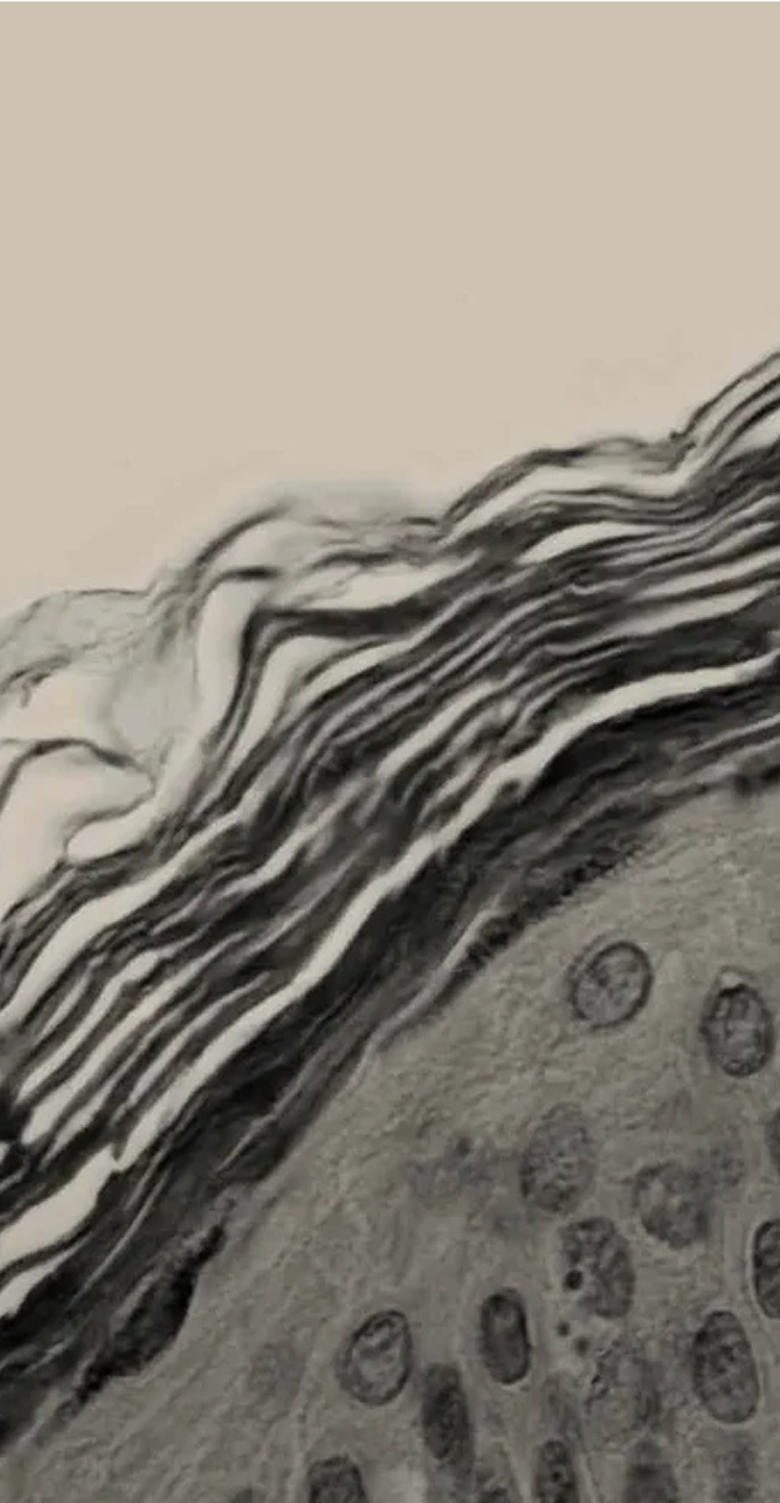

The skin has epidermal units that are responsible for melanin production and distribution, a process called melanogenesis. These units are composed of a melanocyte surrounded by keratinocytes and regulated by a closed paracrine system. Melanin is the primary determinant of skin, hair, and eye colour. And plays a critical role in photo protection due to its ability to absorb ultraviolet radiation (UVR).